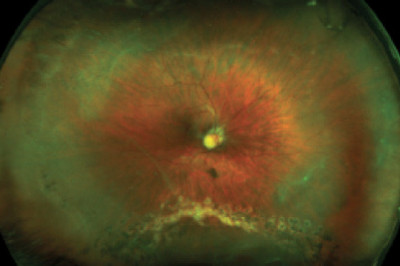

Pediatric vitrectomy is a surgery, which is performed on children to remove vitreous gel from middle part of the eye. Vitrectomy are of two types such as pars plana vitrectomy and anterior eye vitrectomy.